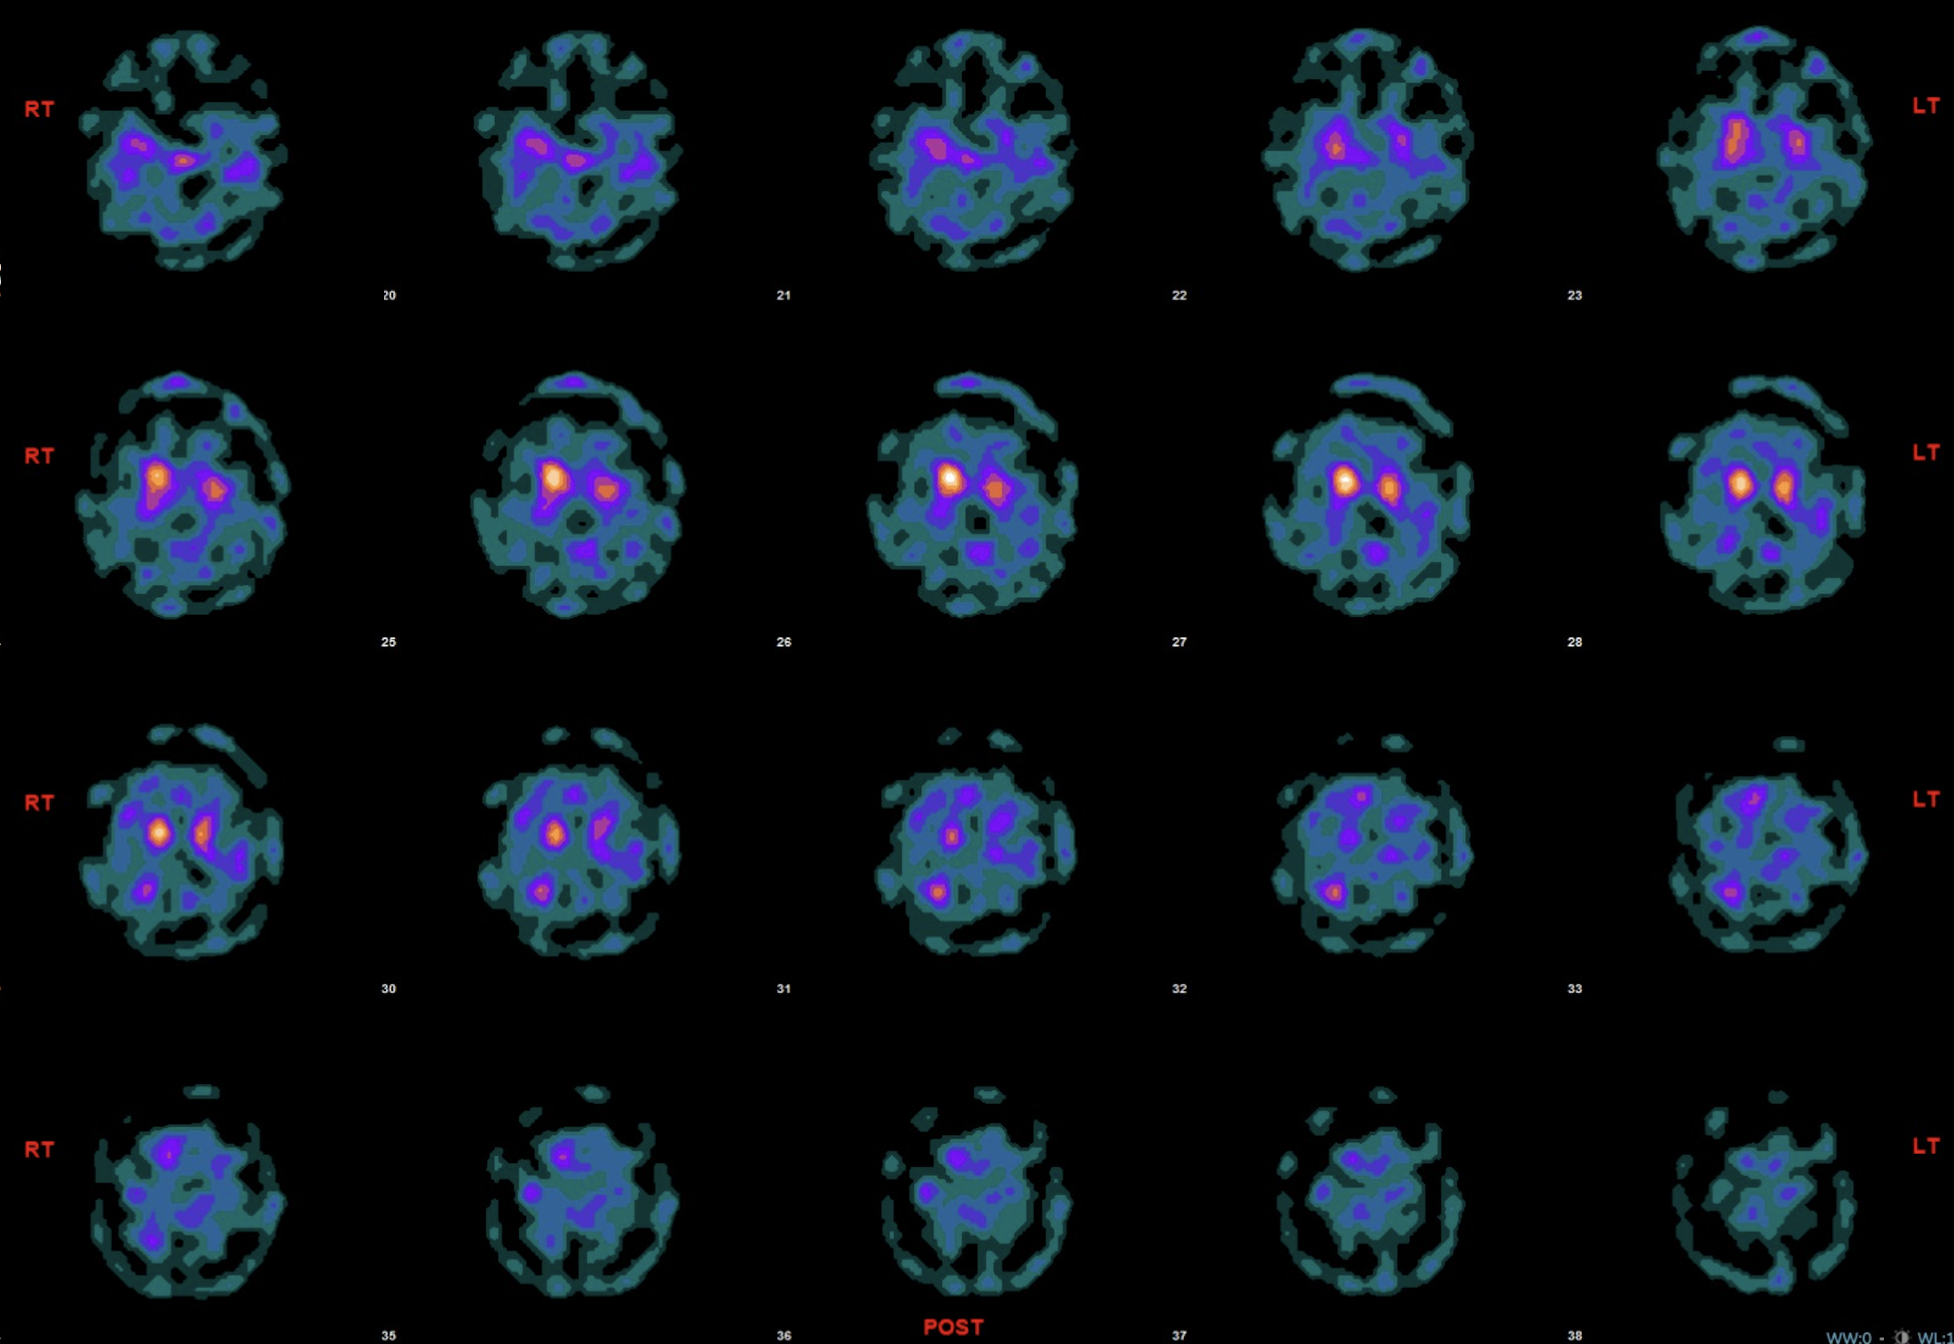

Results: A 37-year-old woman with consanguineous parents presented for evaluation of progressive gait difficulty and bilateral lower extremity pain that had been present for two years. She reported abnormal curling of her toes and stiffness in her legs. Initial evaluation included a brain MRI that showed cerebral and cerebellar atrophy. EMG/NCS was normal. Given her dystonic and parkinsonism features, she was started on carbidopa/levodopa with moderate improvement in her symptoms but significant nausea and wearing off. Genetic testing for dystonia was done and showed a homozygous VUS in PLA2G6, exon 4, c.609G>A (silent), with RNA analysis indicating an altered splicing pattern that could result in the loss of 3 amino acid residues. A DaTscan showed decreased bilateral uptake in the striatum [figure 1]. Bilateral GPi DBS was implanted with good response at 3.0mA/100PW/65Hz (L) and 3.2mA/100PW/65Hz (R), although with persistent balance difficulties.

Figure 1